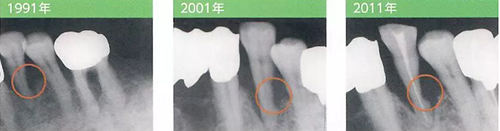

病例3 雖然只進(jìn)行了一次SRP,但預(yù)后發(fā)生了巨大改變

牙周探診SRP

1991年

左下4有較深的牙周袋和BoP,因此用手動(dòng)刮治器進(jìn)行了徹底的SRP。SRP后患者數(shù)次來(lái)復(fù)診,每次都反應(yīng)有牙齒過(guò)敏,最后就不來(lái)醫(yī)院了。

2001年

SRP后10年,由于劇烈的疼痛前來(lái)就診希望進(jìn)行拔髓。雖然只進(jìn)行了一次SRP,但是左下4的牙根遠(yuǎn)中面出現(xiàn)了明顯的缺損。

2011年

在感染控制的前提下,10年間持續(xù)進(jìn)行了牙菌斑去除,沒有再發(fā)現(xiàn)BoP。牙周袋也閉鎖了。但是遠(yuǎn)中面硬組織的缺損仍然發(fā)展顯著。